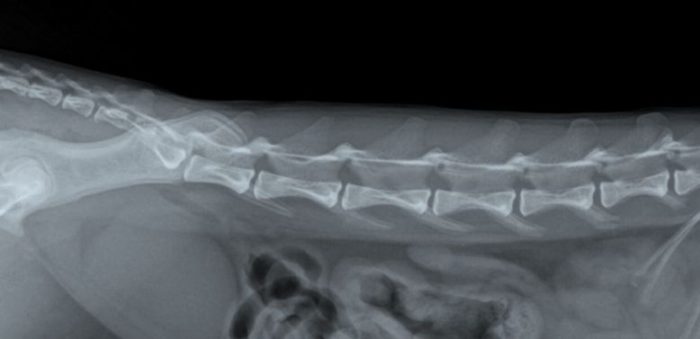

Artrose bij een hond

In de onderstaande foto’s is het verschilt te zien tussen een ruggenwervel van een hond zonder en met artrose. Hierbij is de artrose aangegeven met rode pijlen. Bij een röntgenfoto beoordeeld de arts of er aanwezigheid is van een versmalling van de gewrichtsspleet, wat duidt op een afname van het kraakbeen.